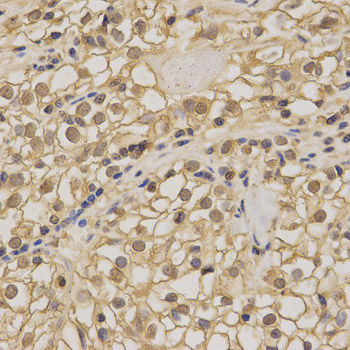

• A0259: image 2

Immunohistochemistry of paraffin-embedded human kidney using NME1 antibody at dilution of 1:200 (x400 lens).